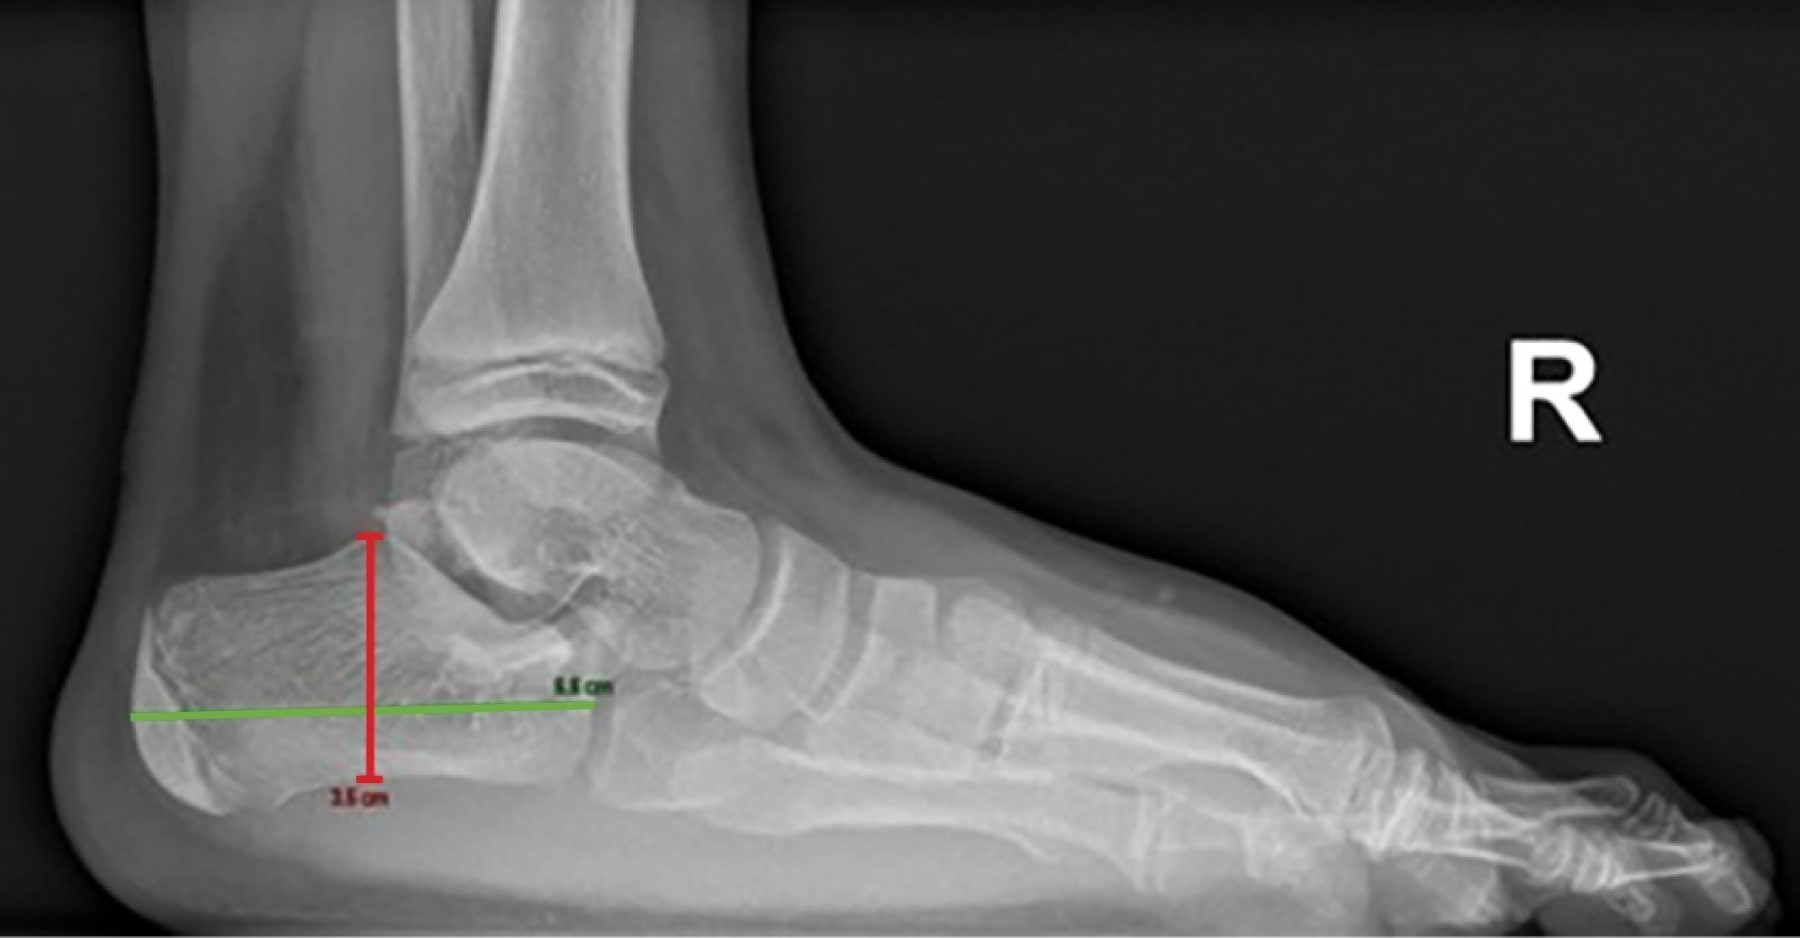

Las radiografías simples de ambos pies mostraron aumento en los espacios intermetatarsianos y del ángulo intermetatarsiano, así como elongación de ambos calcáneos en comparación con los valores esperados para la edad del paciente (Figuras 5, 6 y 7).

Figura 5

Figura 6